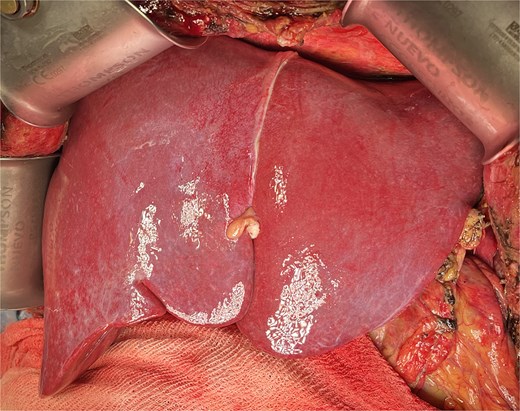

The liver appeared enlarged, heterogeneous, with peripheral necrosis (Fig. 3). The portal vein and previously constructed mesenteric-portal graft were patent. The hepatic artery was thrombosed throughout its course (Fig. 4). Arterial thrombectomy revealed an extensive clot extending into the splenic artery. Dissection continued proximally until healthy arterial walls and adequate flow were confirmed.

Intraoperative view of enlarged liver with heterogeneous texture and peripheral necrosis.